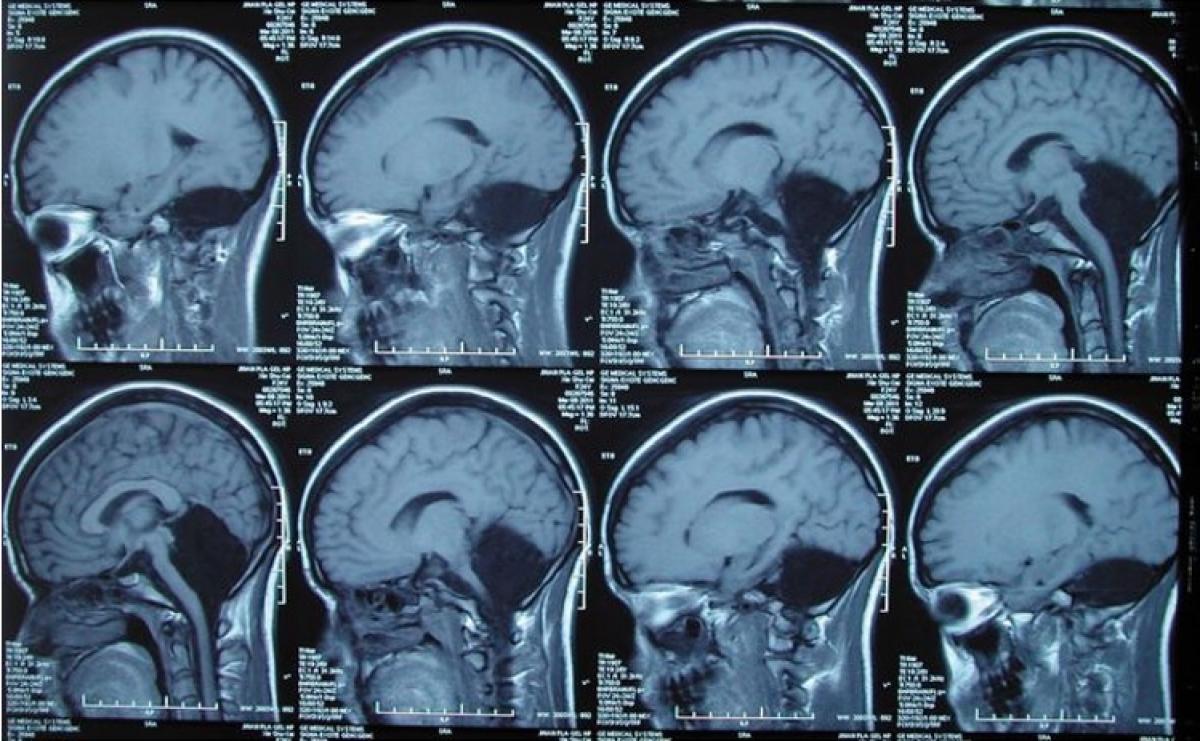

Mai precis, femeia s-a născut fără creierul mic. Medicii au descoperit că nu are cerebel la vârsta de 24 de ani când i-au scanat creierul, după ce aceasta s-a plâns de grețuri și vomă timp de o lună întreagă. Deși lipsa cerebelului ar fi trebuit să indice grave probleme de pronunție și imobilitate, femeia le-a spus că singura problemă pe care a avut-o toată viața fost starea de amețeală permanentă. Ce se afla în locul cerebelului? Lichid cefalorahidian.

Surpriza a fost atât mai mare pentru doctori cât simptomele obișnuite lipseau. Cerebelul controlează toate mișcările, până și cele fine, ca ale gurii și limbii. Chinezoaica însă putea să vorbească normal, oamenii percepând doar un sâsâit ciudat. „Acest caz arată că, la tineri, cerebelul tinde să fie mult mai flexibil și ușor adaptabil la anormalități”, a spus Dr. Raj Narayan, profesor de neurochirurgie la North Shore University Hospital, din New York.

Când o persoană se naște cu o anormalitate sau pierde la o vârstă fragedă o parte din creier, restul creierul încearcă să compenseze.